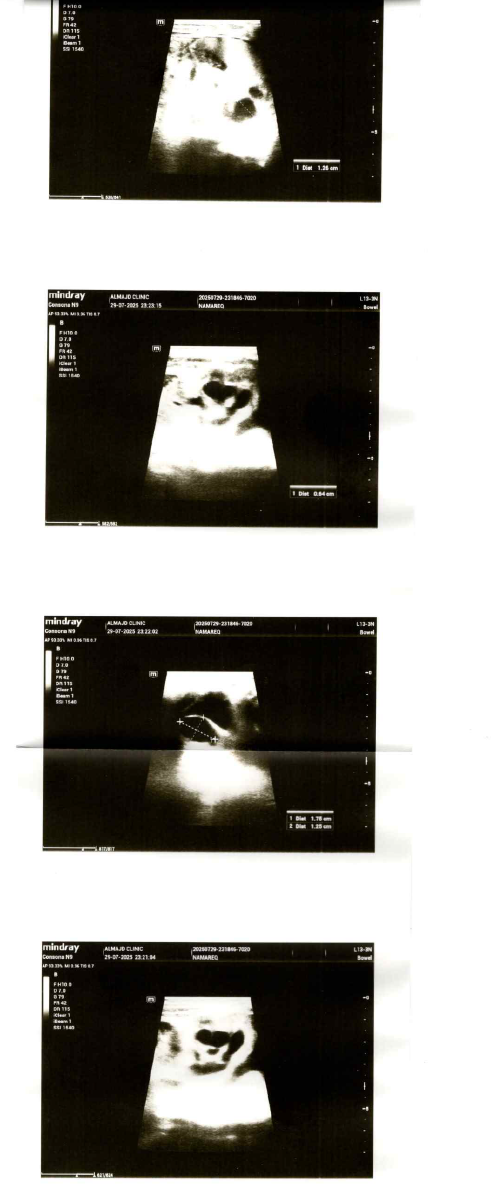

صورة مرفقة

شاهدت الصورة

وهناك توسع في الحالب

وبما أن التوسع أكثر من 7 ملم فيجب العلاج